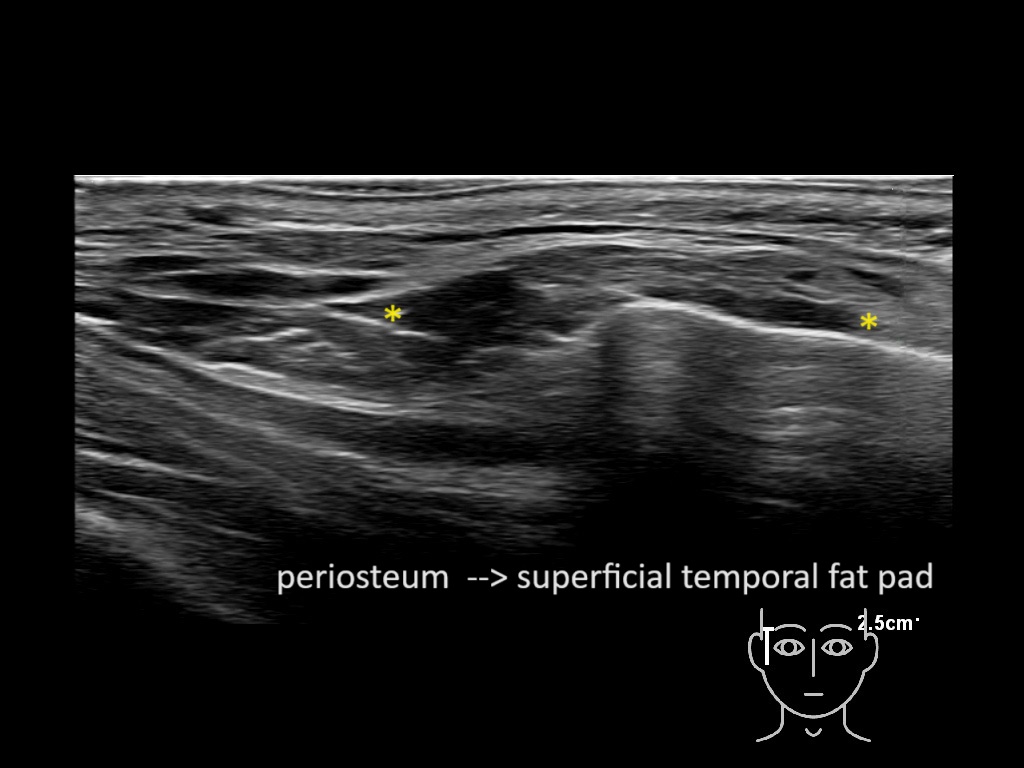

Filler behavior - Temple zygoma US

Study the first image to recognize the different layers. If you are sure about the layers, swipe to the second image to view the answer (if applicable).